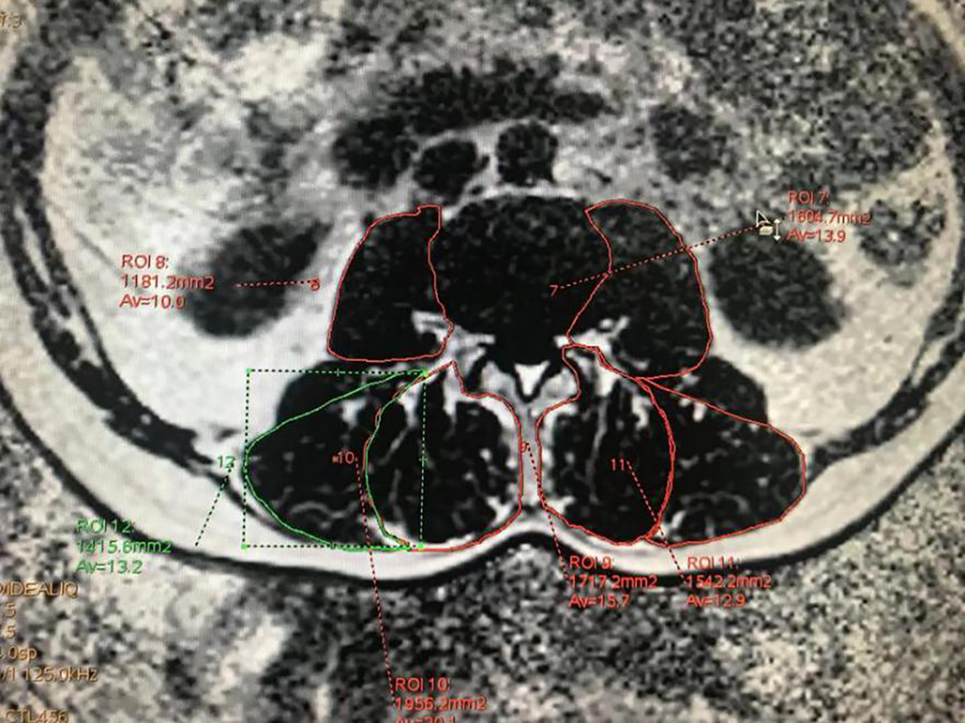

应用GE AW 4.6工作站的Fat Fraction程序对扫描获得的腰椎横断位IDEAL-IQ序列中的fat fraction图像进行后处理,沿肌肉外轮廓勾画所有L1~S1椎间盘中心层面椎旁肌感兴趣区(region of interest,ROI),避开肌肉周围脂肪组织,椎旁肌ROI分别设在两侧多裂肌(multifidus muscle,MF)、竖脊肌(erector spinae,ES)和腰大肌(psoas major,PS) (图2),系统自动生成勾画区域的脂肪百分比(fat fraction,FF)及横截面积(cross sectional area,CSA),为了提高准确性,左右各测量三次取平均值。

采用Artificial intelligence kit (AK,version 3.3.0,GE Healthcare)在腰椎横断位IDEAL-IQ序列中的fat fraction图像中标注所有L1~S1椎间盘中心层面椎旁肌ROI,避开肌肉周围脂肪组织沿肌肉外轮廓标注椎旁肌ROI (图2),共获取2910个标注。每个ROI自动生成影像组学特征186个,包含直方图(histogram)特征与灰度共生矩阵(gray level cooccurrence matrix, GLCM)特征参数,为了提高特征的稳定性和可重复性,每个ROI均标注三次,提取参数三次取平均值。